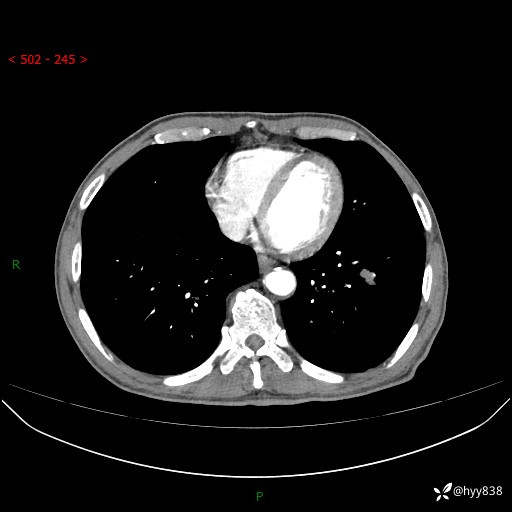

胸部CT平扫

增强动脉期+静脉期

各期CT值:38Hu 52hu 55hu